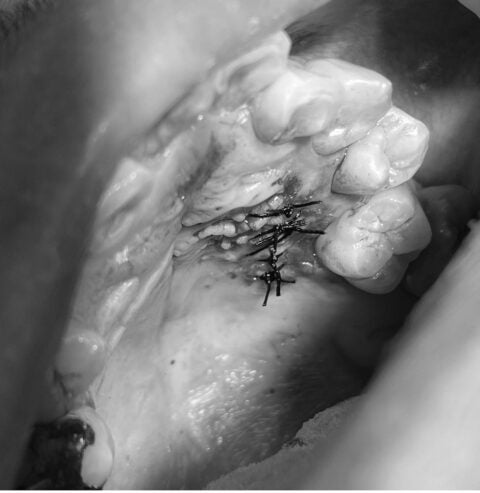

さて、本日は矯正前処置の埋伏歯の抜歯のご症例の紹介です!抜歯手術のが画像(モノトーン処理)がありますので、苦手な方はご注意ください。

患者様には、無痛リラクゼーション治療で完全に眠っている間に手術を終える事ができました。

実際の処置時間は30分弱、鎮静導入から覚醒まで約1時間で終了しました。

患者様には覚醒後、歯をお見せしながら無事に抜歯が出来た事をご説明させて頂きました。(苦手な方はお見せしましせんのでご安心下さい。)